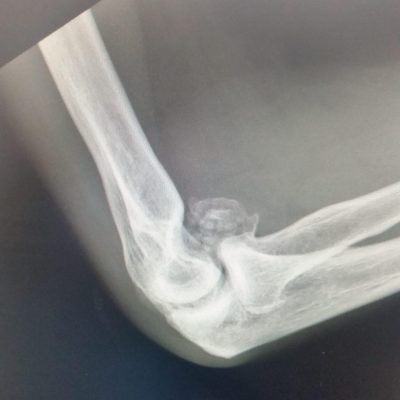

Elbow osteoarthritis is a degenerative joint disease where the smooth cartilage covering the bone ends, wear out, causing pain and stiffness. It can affect younger patients where a previous traumatic injury can lead to either ligamentous instability, severe scarring in the joint or cartilage injury and lead to progressive stiffness around the elbow which may or may not be accompanied by pain.

In cases where the main complaint is stiffness in the elbow, common activities like shaving, getting to the back of the head and face become difficult. X-Rays are a simple scan that can confirm extra bone formation in the joint which may be blocking movement. In these situations, a keyhole operation (arthroscopy) can be performed to remove loose fragments of bone, remove extra bone and release the tight capsule that surrounds the joint.

Pain in the elbow can relate to the inflammation of the joint lining (synovitis) that accompanies osteoarthritis or impingement related pain at the end ranges of movement where bone fragments can jam between the joint surfaces. If loose bodies are present in the joint, these can float around freely and intermittently cause jamming of the moving parts like a loose stone in a motor. Depending on the cause of pain, the treatment can be directed at reducing the inflammation with oral anti-inflammatories or corticosteroid injections to the joint. Surgical treatments include arthroscopic or open debridement of the joint to remove extra or loose fragments of bone that are impinging. If there is extensive joint involvement and these simple measures fail to relieve pain then a Total Elbow Replacement can provide good pain relief whilst maintaining movement.